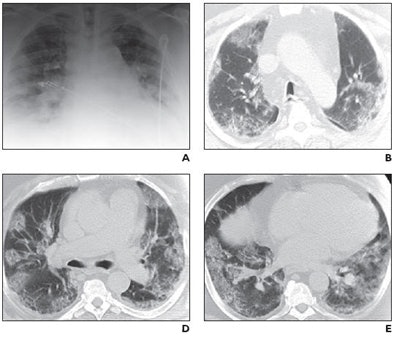

| Middle-aged man with no history of chronic pulmonary disease presented to emergency department with five-day history of fever, fatigue, nausea, diarrhea, and cough. Radiography and CT were performed. Unenhanced chest CT lung window images showed multifocal peripheral ground-glass opacities involving all lobes. Patient died on fifth day. Above: A, Chest radiograph obtained at clinical presentation shows peripheral opacities. B, Unenhanced chest CT lung window image shows apical patchy peripheral ground-glass opacities. D, Unenhanced chest CT lung window image reveals that lingula, right middle lobe, and both lower lobes show patchy, peripheral, rounded, peribronchial ground-glass opacities with air bronchograms. E, Unenhanced chest CT lung window image shows bilateral lung bases with ground-glass opacities still predominantly patchy at periphery, but more confluent ground-glass attenuation. Below: C, Unenhanced chest CT lung window image reveals that upper lobe and superior segments of both lower lobes show peripheral peribronchial ground-glass opacities. F, Magnified view of anterior segment of right upper lobe shows ground-glass opacity peripherally and air bronchograms (arrows). Images used with permission of the American Roentgen Ray Society. |

"Many of the opacities showed air bronchograms with normal-sized bronchial airways leading into each rounded ground-glass focus, and most large airways showed no significant wall thickening or plugging," Mollura et al wrote of the CT findings. "The ground-glass opacities were located throughout the upper and lower regions of all lobes in a peribronchovascular distribution. CT showed no evidence of a mosaic perfusion pattern, suggesting no localized air trapping or regional changes in blood flow."

No centrolobular nodularity or tree-in-bud opacities were seen, suggesting an absence of small-airway inflammation in the secondary lobules. IV contrast media could not be given due to the patient's progressing renal failure, the group noted.

Chest CT in soft-tissue windows showed an absence of mediastinal lymphadenopathy, or pleural or pericardial effusion. Echocardiography showed "moderate concentric left ventricular hypertrophy and an ejection fraction of 58% with mild-to-moderate tricuspid regurgitation," they wrote.

The fatal case of H1N1 influenza A virus (S-OIV) revealed a pattern of rounded peripheral ground-glass opacities on CT that can also be seen on severe peribronchial air-space disease, but were shown radiographically to differ from cardiogenic edema.